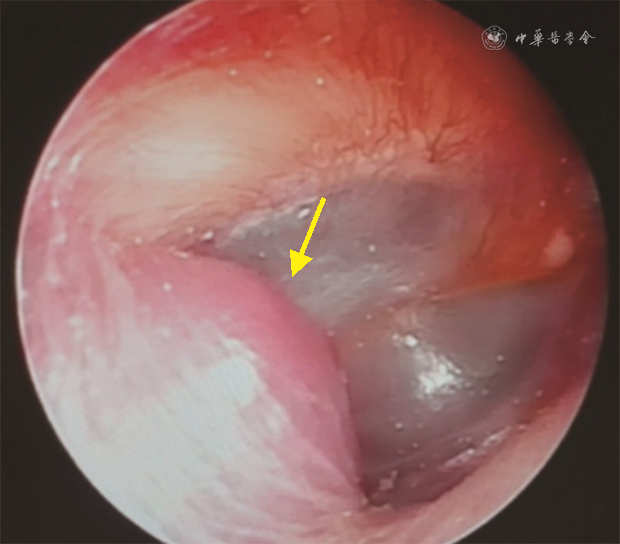

体检可发现位于完整鼓膜后方的樱桃红色搏动性新生物,新生物可突破鼓膜进入外耳道,表现为外耳道新生物(图1)。颈静脉孔区其他类型肿瘤也可在鼓膜后方或外耳道形成新生物,然而由于血供没有副神经节瘤丰富,其外观颜色不如副神经节瘤鲜红。由于肿瘤多侵犯或压迫邻近骨质或颅神经,颅神经损伤常为主要表现。颅神经损伤的出现次序和损伤程度与肿瘤位置和起源有关,如肿瘤向后上发展累及面神经可导致口角歪斜,闭眼欠佳,Ⅸ~Ⅺ颅神经受损可出现颈静脉孔综合征,病变扩大累及Ⅻ颅神经可能会出现患侧舌肌萎缩。